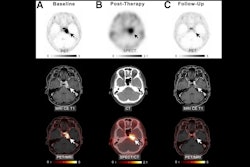

Brain metastases tend to be treated by either whole-brain radiation therapy (WBRT) or a "conformal" protocol that targets radiation dose to the tumor site, the group noted. Common types of conformal radiation are stereotactic radiosurgery (SRS) -- which imparts fewer but higher doses of radiation per treatment to the tumor site -- and hippocampal avoidance WBRT, which limits delivery of radiation to the parts of the brain that have been shown to manifest neurocognitive side effects following treatment, it explained. But how patients treated with targeted radiation are affected long-term has not been determined.

Cognitive side effects from radiation therapy can include decreased executive function, learning ability, and memory, the authors wrote. They explored whether brain cancer patients who experience these side effects eventually recover their cognitive health via a study that included data from 288 patients with long-term cognitive testing data; the group compared whole-brain radiation therapy with different types of targeted radiation treatment. Patients underwent a series of cognitive tests before radiation therapy and six and 12 months after the loss of cognitive function.